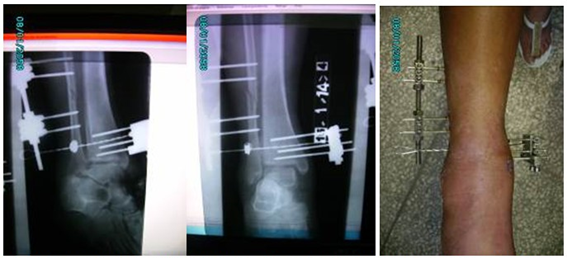

Para enfrentar esta combinación de lesiones se preparó un mini fijador RALCA con dos cuadriláteros, se trenzó un alambre calibre 18 para ser usado como método de fijación sindesmal y se empleó un cuadrilátero aparte para anclar el alambre de sujeción sindesmal por la cara medial del tobillo.

Se muestran imágenes del procedimiento quirúrgico y rayos X del posoperatorio. (Fig. 2 y 3).